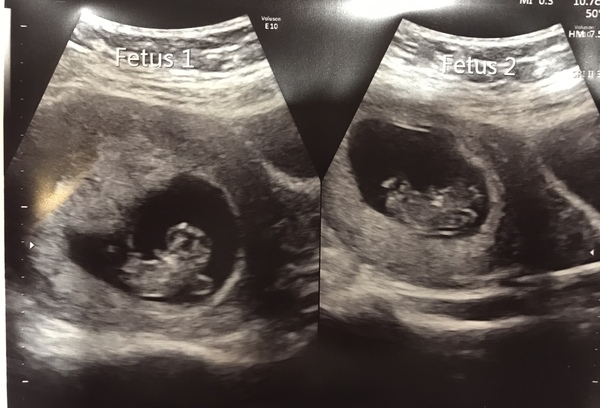

Hi everyone, not been on for a while although been keeping up with everyone else’s news! Sorry to hear of anyone else still feeling rough (like me) but yay to all those who have gorgeous scans to look at!! I had a private scan this morning, all went great, heard 2 healthy heartbeats, Dr said both measuring pretty much the same although they’ve put me further ahead by 3 days so 9+5 today - I’ll take it!! Got my nhs scan letter through the other day, it’s not until the 21st of November though, seems ages away and will be 13+3 then, just seems so late, but because I’m classed as high risk I can only go to one specific hospital for my scans instead of the choice of 3 in my last pregnancy so I guess I’ll have to take what I can get...

@JBFletcherstypewriter lovely scan photos of the twins! 💕

@ JBFletcherstypewriter such lovely twinny pictures. So sorry to hear about your DH. Hope his scans come back positive for you. Must be so stressful.

@JBFletcherstypewriter beautiful scan pictures. congratulations. i'm sorry i think i missed what you mean about your husband- is this an old or new problem? what do they think it is? so sorry he has to go through this when u have the double blessings growing inside. fingers crossed all turns out to be ok x